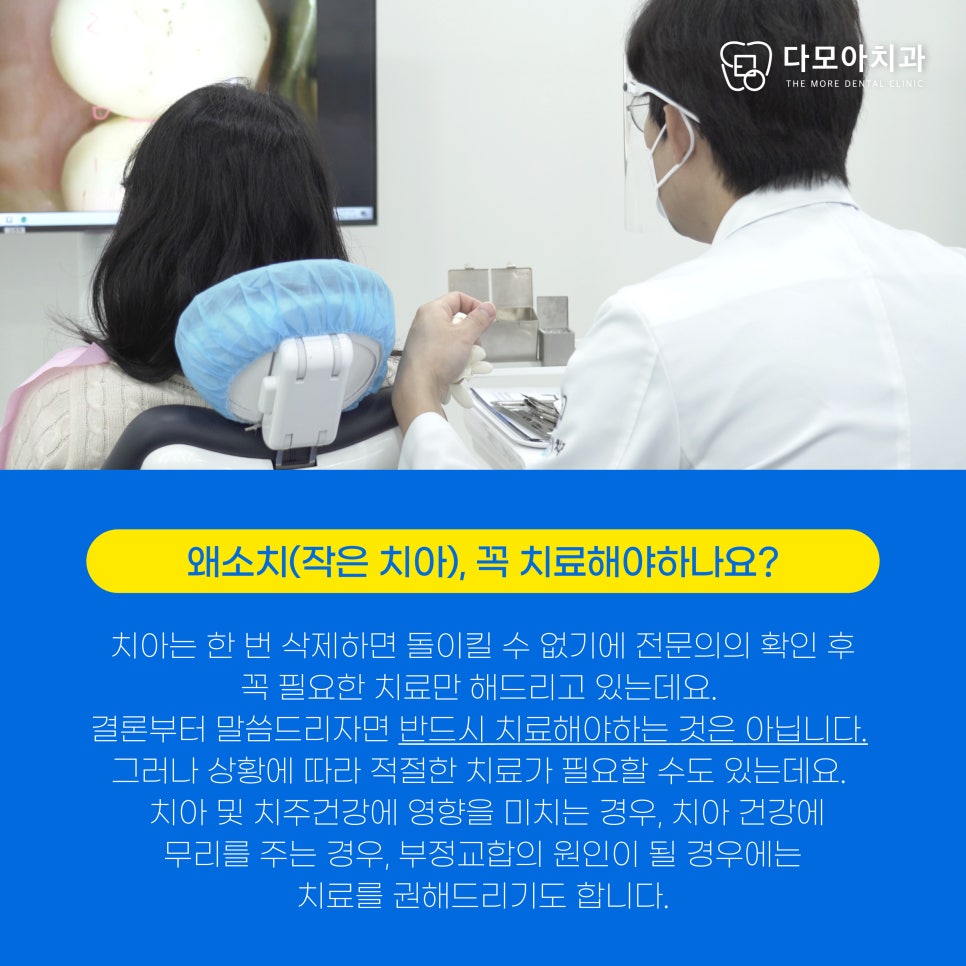

이번에 내원해 주신 환자분은

이전에 다른 병원에서 이미 왜소 치아로

라미네이트 치료를 받은 전적이 있으셨는데요.

라미네이트 깨짐으로 다모아치과에 내원해

재치료가 필요한 상황이었습니다.

사진 속 라미네이트 한 부분이 깨지고,

2차 우식이 일어난 부분이 보이시나요?

우선 X-ray로 기존 치아를 확인해 보았습니다.

앞니 양옆의 치아가 특히 작고,

뒤틀려있어 치아 간 공간이 컸기 때문에

왜소치가 치아 건강 및 교합에

좋지 않은 영향을 미칠 것으로 예상되었는데요.

치아 우식과 깨짐을 보강하여

라미네이트 재치료 받는 것을 원하셨습니다.